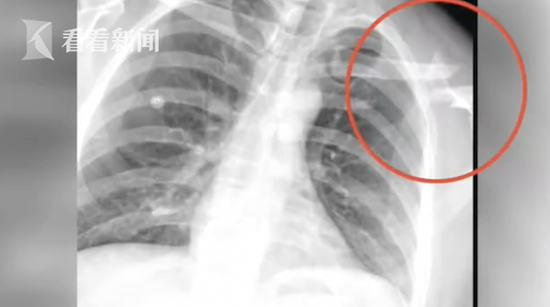

当天吴先生被确诊为左锁骨粉碎性骨折。手术后,吴先生骨折处植入了一块钢板,11天的住院治疗共花费了1万7千块钱。